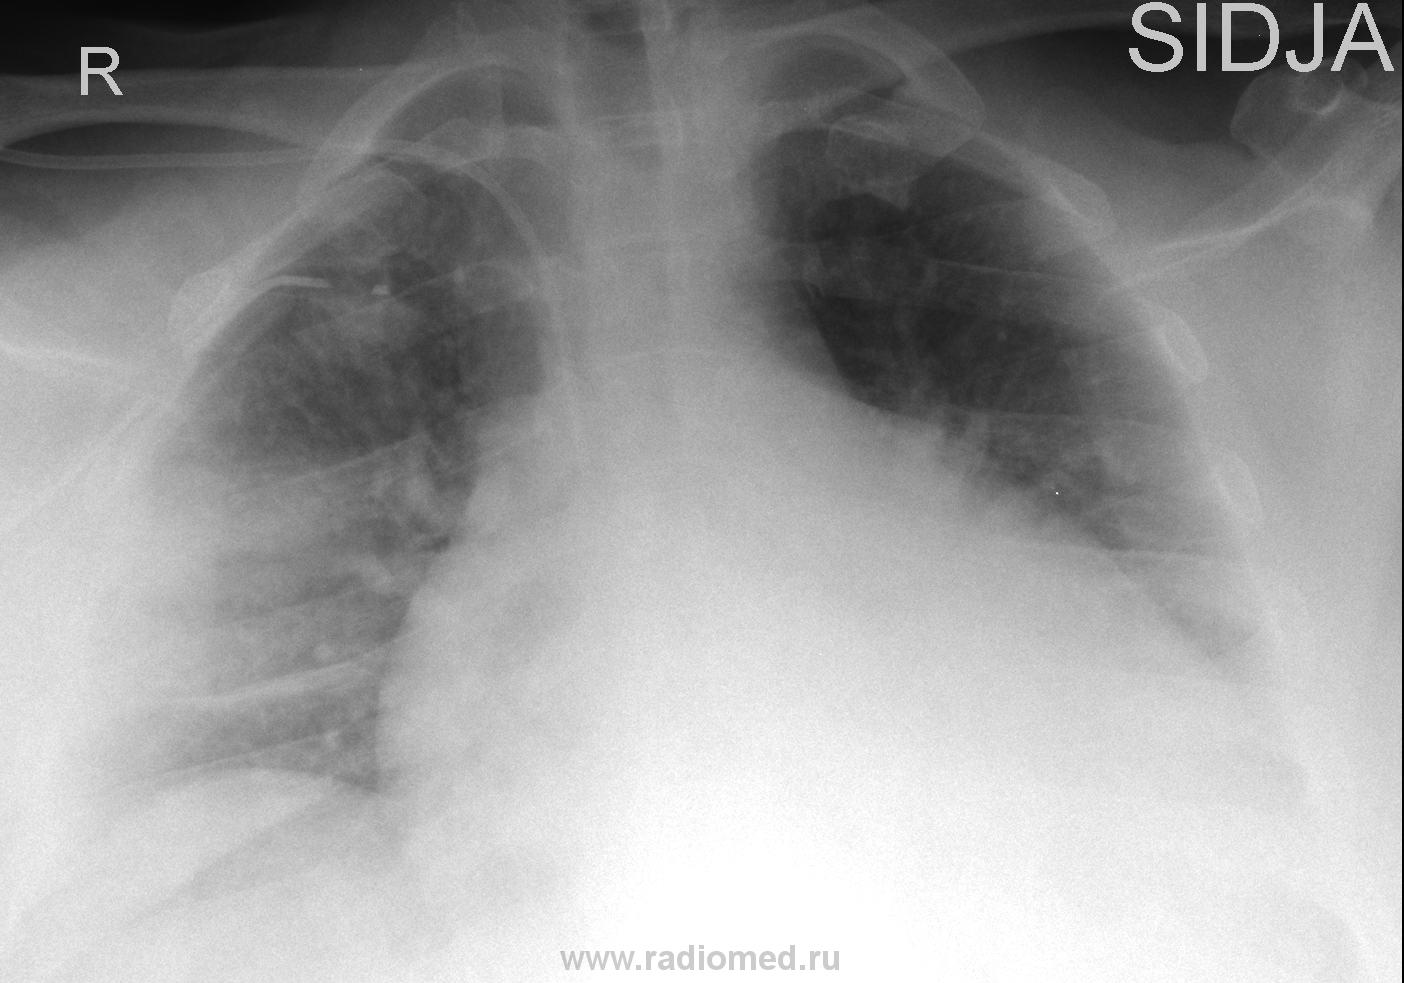

Вчера на дежурстве привозят мне женщину с кардиохирургии, рентген-контроль через 2 часа после плевральной пункции:

Напрашивается вопрос на основании чего делали пункцию, а на основаннии УЗИ, написали до 6см жидкости, пропунктировали, в действительности получили 1л. жидкости, а вот последствие явно на большее тянет.

Андрей Юрьевич, как "классический рентгенолог", прав на все 100%. На латерограмме было-бы отображение жидкости - выпот не осумкованный - растекся-бы. Если-бы был-бы сделан снимок в положении лёжа (на спине), то в результате растекания жидкости было-бы снижение прозрачности правого лёгочного поля, и сопоставив два снимка - в ортоположении и в положении лежа, вывод о наличии наддиафрагмального плеврита выполз-бы сам собой. По всей видимости "снимок после пункции" и был произведен в положении лёжа, вот и "недопунктированное" количество жидкости растеклось.

Всё же данная картина была описана как наличие гемопневмоторакса с компрессионным ателектазом легкого. Плотность жидкости варьирует в пределах 30-55HU. Сделали контроль после дренирования: